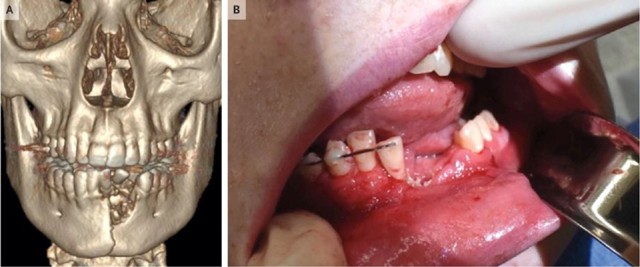

Theo báo cáo của Tạp chí Y học New England được công bố vào ngày 19/6, bệnh nhân nhập viện trong tình trạng có nhiều vết thương ở miệng, nhiều răng bị mất và hàm dưới bị gãy. Bác sĩ Katie Russell cho thiếu niên cho biết, trong quá trình điều trị, họ đã phải nhổ vài cái răng ra khỏi miệng vì chân răng vị vỡ, đồng thời đặt một tấm lưới nha khoa ở dưới nướu để ổn định xương hàm.

Nhưng sau đó miệng cậu bé vẫn không khép lại được, cuối cùng các bác sĩ đã bịt hàm bệnh nhân lại trong 6 tuần để vết thương có thời gian chữa lành.

Về phần nhân vật chính ở câu truyện trên, nạn nhân đã quyết tâm cai hoàn toàn thuốc lá. Sau 1 năm, các vết thương đã lành trở lại và cậu bé chuẩn bị trồng răng để lấy lại nụ cười.